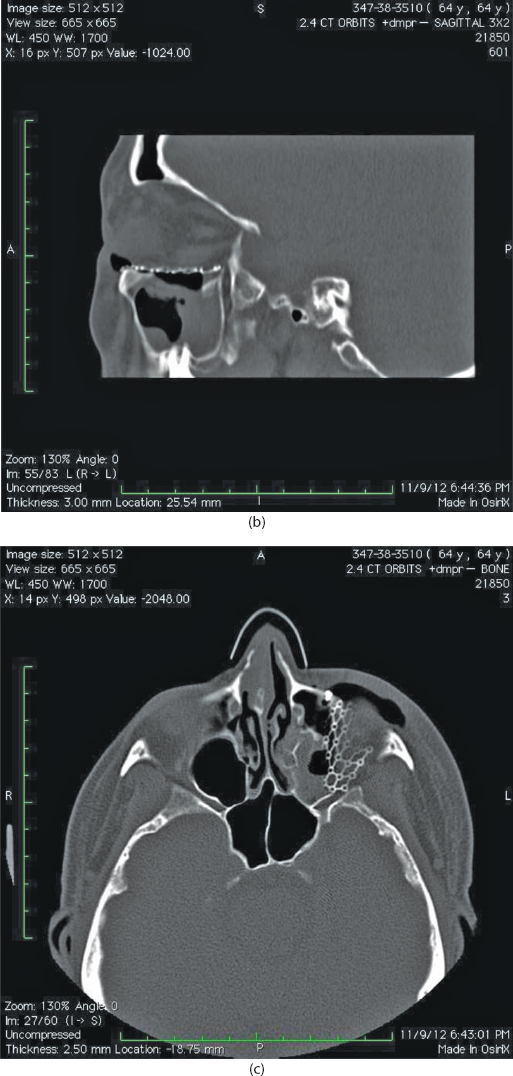

Isolated orbital floor fractures (blowouts) are often the result of impact injury to the globe resulting in a sudden increase in intraorbital hydraulic pressure. This kinetic energy is transmitted in an inferior and medial vector to the orbital floor (hydraulic theory) (Figure 13.1). Alternatively, the posterior transmission of a direct blow to the infraorbital rim causes buckling and resultant fracture of the orbital floor (buckling theory) (Figure 13.2). Fractures of the orbital floor can increase the volume of the orbit with resultant enophthalmos and hypoglobus. These can be highlighted on preoperative (Figure 13.3a–c) and postoperative (Figure 13.4a–c) computed tomographic (CT) scan imaging. In addition, the inferior rectus or periorbital soft tissue can become entrapped within the fracture line, resulting in restriction of extraocular eye movements. Table 13.1 indicates the special equipment used to surgically manage this injury.